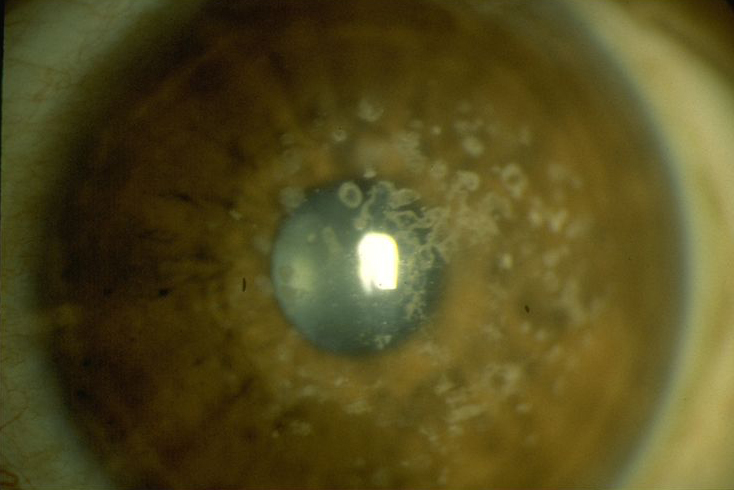

The cornea is the clear window in front of the eye. If it is not clear the patient can’t see. This patient has a corneal ulcer that requires urgent treatment.